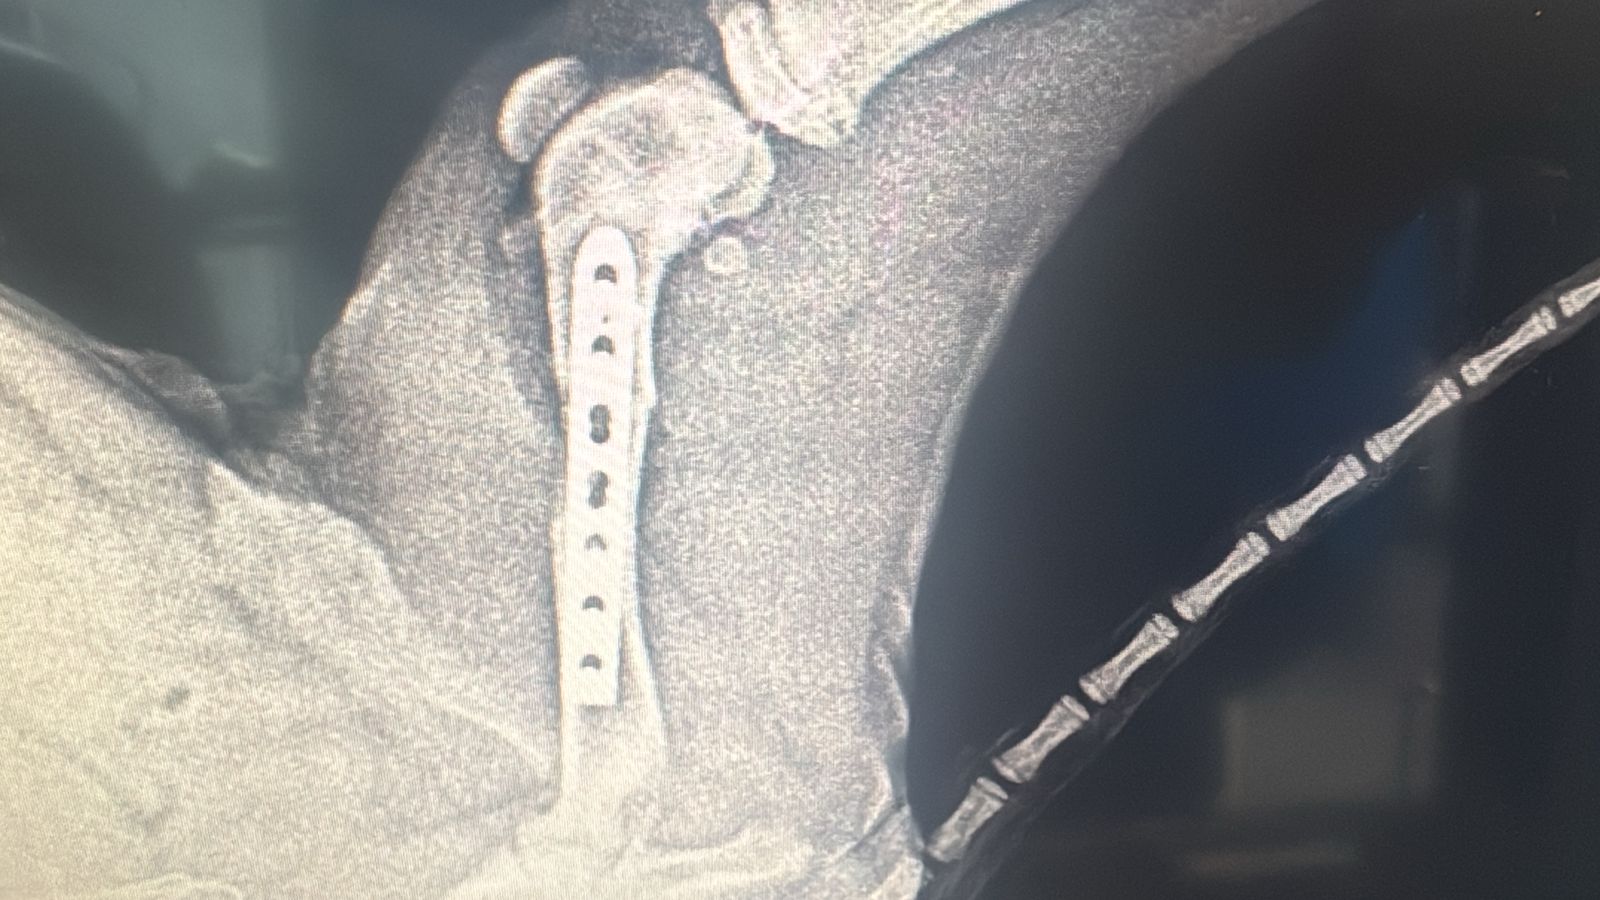

Vali was hit by a car on the airport road . He had one broken front leg, one broken back leg and one broken pelvis. He’s very scared. He’s good with other dogs. DOB: 10/10/2024